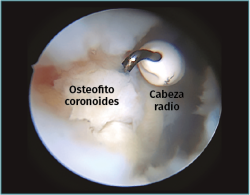

Figura 2. Visión artroscópica desde el portal anteromedial de un osteofito en la coronoides, disecado con un vaporizador de gancho, previamente a su resección con fresa motorizada.

Trabajaremos la parte ósea en primer lugar, resecando los osteofitos de la coronoides y de la fosa coronoidea, así como de la cabeza radial o de la articulación radiocubital si fuera necesario. Una vez hemos finalizado la parte ósea, procederemos realizar la capsulotomía anterior si está indicada.